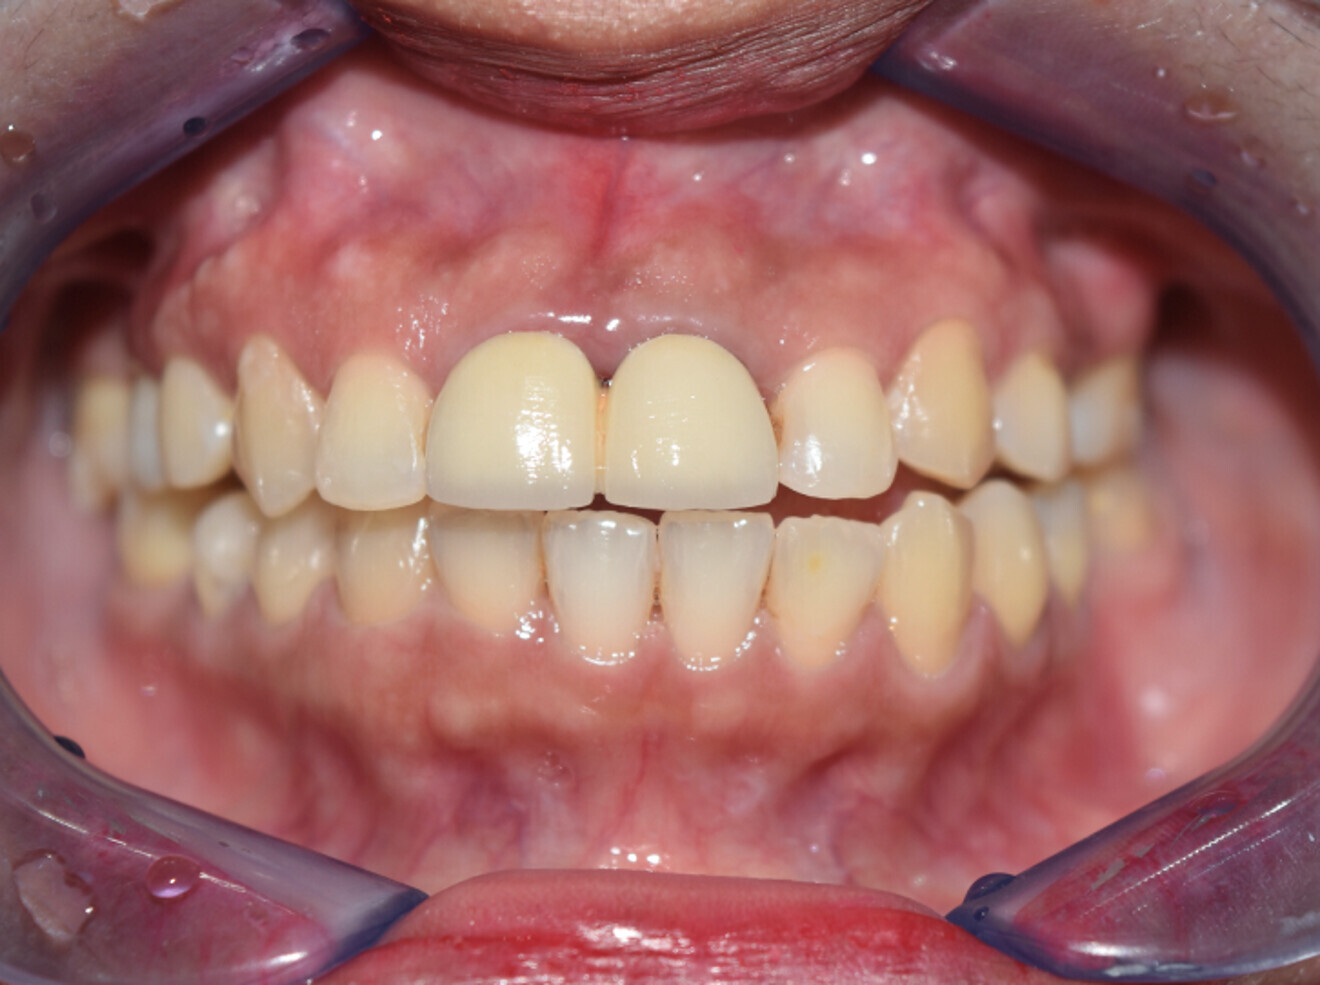

Case 2

• 50-year-old woman

• No underlying medical condition.

• Main complaint: Multiple gaps.

Intra-oral findings:

Class I malocclusion with poli diastemas in both upper and lower arch.

Overbite= 1mm Overjet = 3mm

No molar classification (absence of molars)

Class I canine on right and left side.

Upper midline (mesial to 11) on with face.

Lower midline on with the chin.